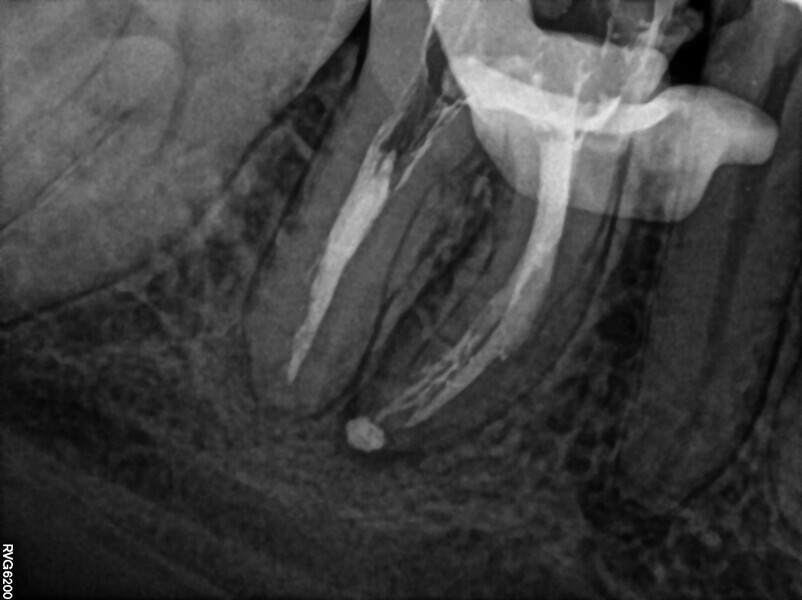

Fig. 20: Intra-op radiograph confirming lack of bypass and of patency.

After administering anaesthesia and placing a dental dam, the composite restoration was removed, and a temporary restoration with flowable composite and flowable dental dam for the root canal treatment was performed (Figs. 14–17). After removing the filling material from the mesiolingual and distal canals, access to the broken file was performed. The first piece of the instrument was removed with the ultrasonic tip (Fig. 18), and the tip of the second piece of the file then became visible. Unfortunately, the removed file piece broke in the middle and only the coronal part could be retrieved (Fig. 19). Because the apical part of the broken file was invisible and did not emerge from the canal during the irrigation and activation, an attempt at bypassing it was made. Analysis of the CBCT scan did not reveal a clear answer as to whether there was one apical foramen, so during the bypass procedure through the mesiolingual canal, a periapical radiograph was performed. The radiograph indicated that either there was a ledge in the apical area or there were two separate apical foramina (Fig. 20). For the irrigation protocol, the AutoSWEEPS mode was used at 1.2 W power with the flat SWEEPS 300/20 fibre tip. The tips of both mesial canals were placed below the orifice. The Less-Prep Endo protocol was performed twice in the manner described elsewhere.5 After the irrigation, irrigant flow between both canals was rapid.